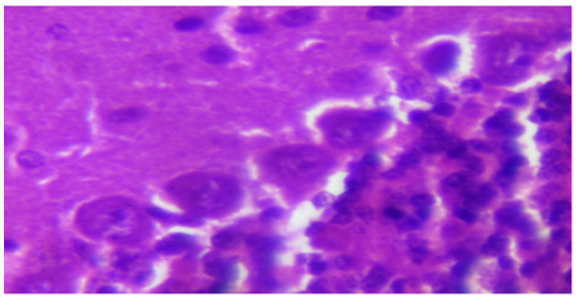

F. THE EFFECT OF ASPARTAME ON THE HISTOLOGY OF THE CEREBELLAR CORTEX

(Plates 1-3).

Plate 1: Photomicrograph of cerebellar cortex of rats administered aspartame at 40mg/kg showing purkinje cells and granule cells. H&E X400.

Effect of Aspartame on Cerebellar Morphology (causes purkinje cell death)

Oral intake of Aspartame in mice has been reported to be the cause of neuronal necrosis in several regions of the brain including the hypothalamus [7,14]. Histological observation of the cerebella cortex shows neurodegeneration of the purkinje cells at aspartame dosage of about 80kg/bw. The neurodegeneration of the purkinje cells might be as a result of activities of aspartame on N-Methyl-D-Aspartate (NMDA) receptors. Aspartame may act on NMDA receptors, leading to continuous activation of these receptor sites resulting in no binding space for glutamate, in which continuous activation of these sites might cause damage to the brain neurons as described by Sara, et al. [8] and Choi and Rothman [15]. This also supports the works of David, et al. [16] that aspartame acts as an agonist of glutamate on the NMDA receptor.